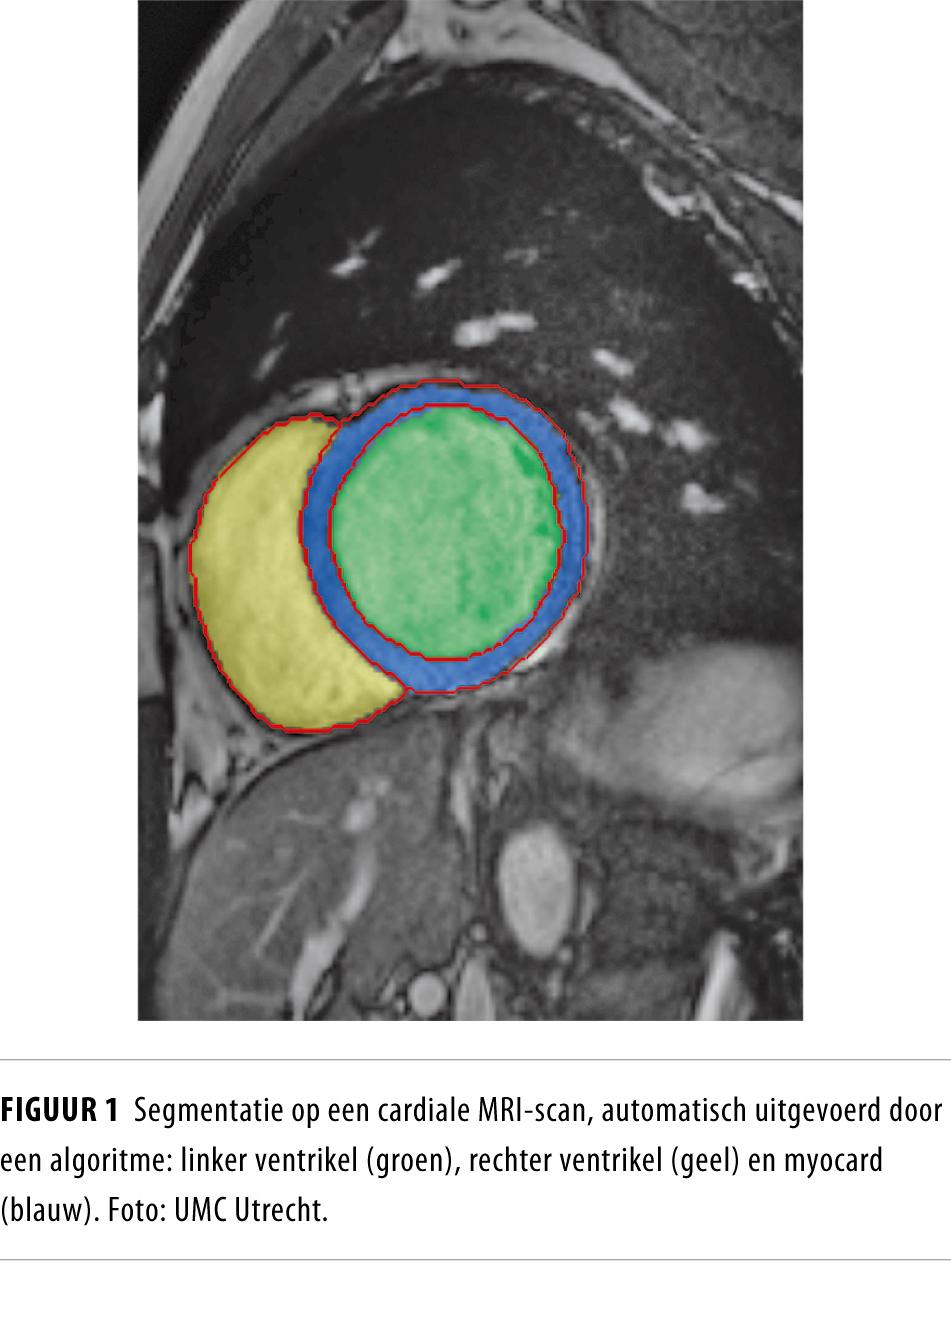

Kunstmatige intelligentie krijgt steeds meer voeten aan de grond in de zorg. Zelflerende algoritmes helpen dokters om beter te voorspellen en diagnoses te stellen. Er zijn zelfs mensen die beweren dat computers het werk van radiologen over zullen nemen. Wat is kunstmatige intelligentie? Zien radiologen hun toekomst somber in?